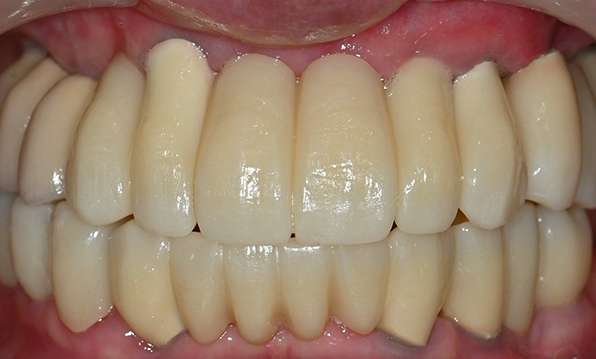

Before & After

| Before | After |